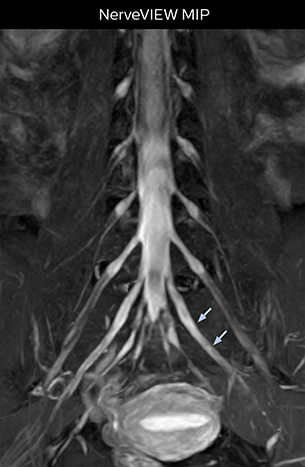

“In patients with lower extremity neurological symptoms, NerveVIEW helps us to determine the disease matching the patient’s symptoms by directly visualizing the nerves. We use the sequence mainly, when there is suspicion of intraforaminal stenosis, extraforaminal stenosis or lateral disc herniation, which is often based on routine T2- and T1-weighted images. Additionally, the excellent depiction of the course of nerves makes NerveVIEW a good navigator when applying treatment such as block therapy or surgery.”

“In such case, we would then browse through axial T2-weighted MR images slice by slice and mentally reconstruct the actual situation based on both radiculography and MRI. Fortunately, NerveVIEW can now very well show nerve courses and presence of nerve compression or edema in one single image series.” “We have often seen NerveVIEW directly depict details of the nerve compression that were not observed by radiculography. Therefore, we think that with NerveVIEW we can reduce the number of invasive examinations, especially for some patients with lumbar plexus symptoms.”

“Although symptoms of typical disc herniation and atypical hernia are very similar, the actual site of herniation is different. It is therefore important to characterize the nerve’s condition both inside and outside of the intervertebral foramina. “Conversely, if we see no abnormality in NerveVIEW, we can assume at least that there is no severe condition that requires surgery. Like this, it can help us avoid unnecessary surgery. NerveVIEW can have a tremendous impact in this way.”

“NerveVIEW can clearly show nerve courses and presence of nerve compression. However, when multiple abnormalities are seen, it can still be hard to determine which nerve is causing the symptoms,” says Dr. Yabuki. “In our experience so far, we see abnormal findings on NerveVIEW in about 70% of elderly patients. As the pain is usually caused by only one nerve, we thus need to find the exact corresponding nerve.” “With a nerve root block, the patient's pain is improved by infiltration of local anesthesia directly around the nerve root considered to be responsible. Knowing such nerve root block findings prior to image interpretation, helps to easily recognize abnormal findings on NerveVIEW as well. In other words, without a priori knowledge, based on symptoms and/or nerve root block findings, we must be aware of the possibility of overdiagnosis.”